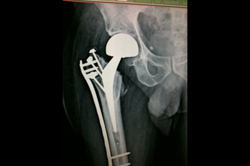

Periprosthetic Fracture THR